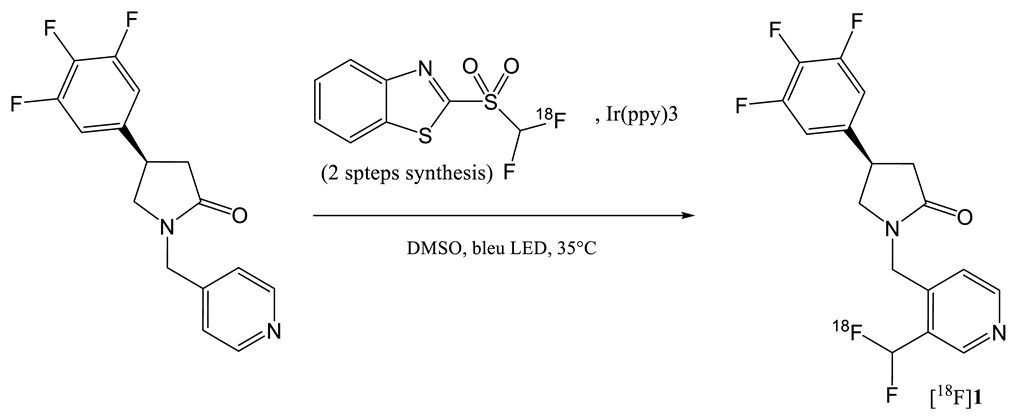

2. Radiochemistry of SV2A PET Radiotracers

- Trump, L.; Lemos, A.; Lallemand, B.; Pasau, P.; Mercier, J.; Lemaire, C.; Luxen, A.; Genicot, C. Late-Stage 18f-Difluoromethyl Labeling of N-Heteroaromatics with High Molar Activity for Pet Imaging. Angew. Chem. Int. Ed. 2019, 131, 13283–13288. [Google Scholar] [CrossRef] [Green Version]

- Trump, L.; Lemos, A.; Jacq, J.; Pasau, P.; Lallemand, B.; Mercier, J.; Genicot, C.; Luxen, A.; Lemaire, C. Development of a General Automated Flow Photoredox 18F-Difluoromethylation of N-Heteroaromatics in an AllinOne Synthesizer. Org. Process. Res. Dev. 2020. [Google Scholar] [CrossRef]

| Entry | Tracer | Ref | Synthesis of the Radiotracer | pIC50 for Human SV2A | Ki (nM) for Human SV2A | Molar Activity (GBq. µmol−1) | RCY (%) |

|---|---|---|---|---|---|---|---|

| 1 | [11C]Levetir-acetam | [18] |  | 5.7 [24] | 2500 | 17 | 8.3 (dc) |

| 2 | [18F]UCB-H | [19] |  | 7.8 | 9.0 | 518 | 15 (ndc) |

| 3 | [21] |  | 815 ± 185 | 35 (ndc) | |||

| 4 | [18F]UCB-A | [23] |  | 7.9 [24] | ND a | 65 | 14 (dc) |

| 5 | [11C]UCB-J | [24] |  | 8.2 | 1.5 | 215 | 35 (dc) |

| 6 | [18F]UCB-J | [27] |  | Similar to [11C]UCB-J | Similar to [11C]UCB-J | 59 ± 36 | 1–2 (ndc) |

| 7 | [18F]SynVesT-1 | [28,29] |  | 8.4 | 2.2–4.7 b | 242 | 19 (ndc) |

| 8 | [18F]SynVesT-2 | [31] |  | ND a | 12 | 141 | 7(dc) |

| 9 | [18F]1 | [33] |  | 8.3 | ND a | 40–80 | 1.5 (dc) |